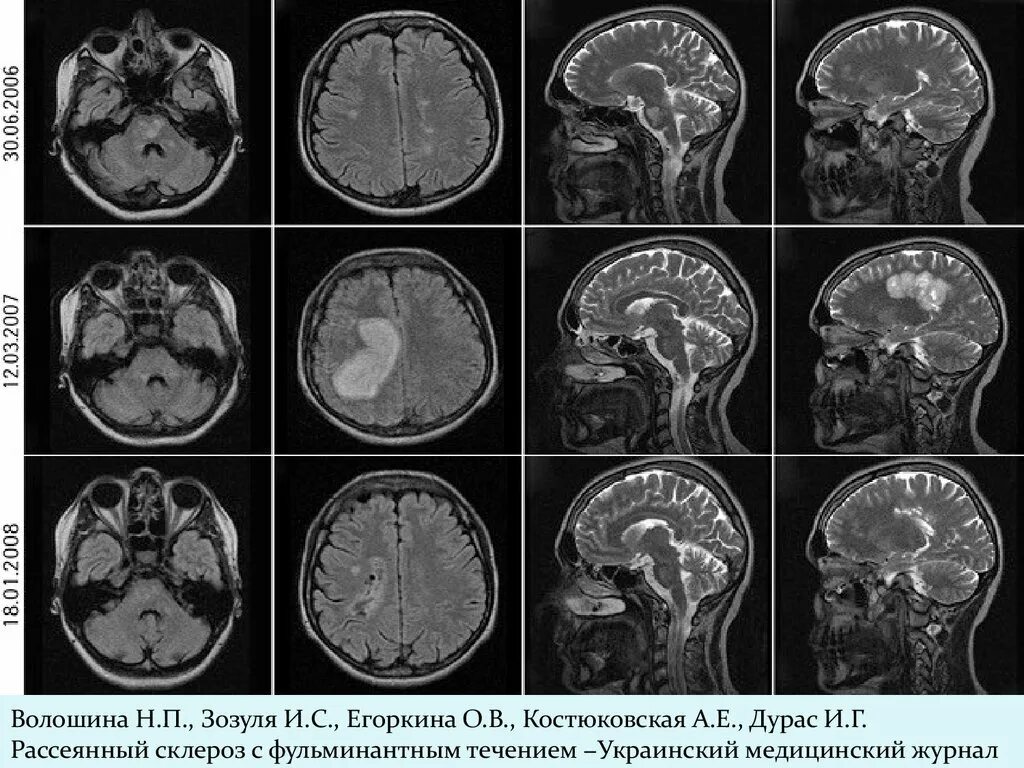

Демиелинизирующее заболевание головного мозга что это такое